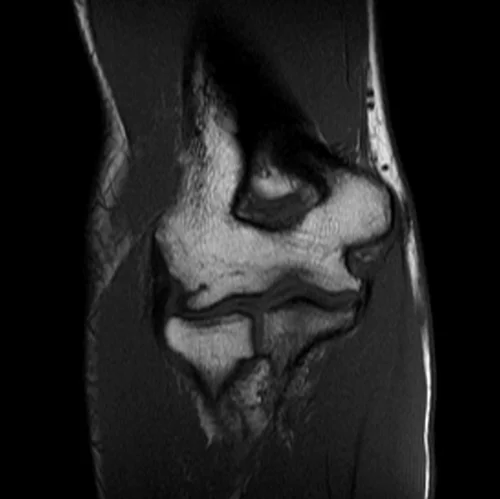

mri elbow coronal t1 image 2 - MRI